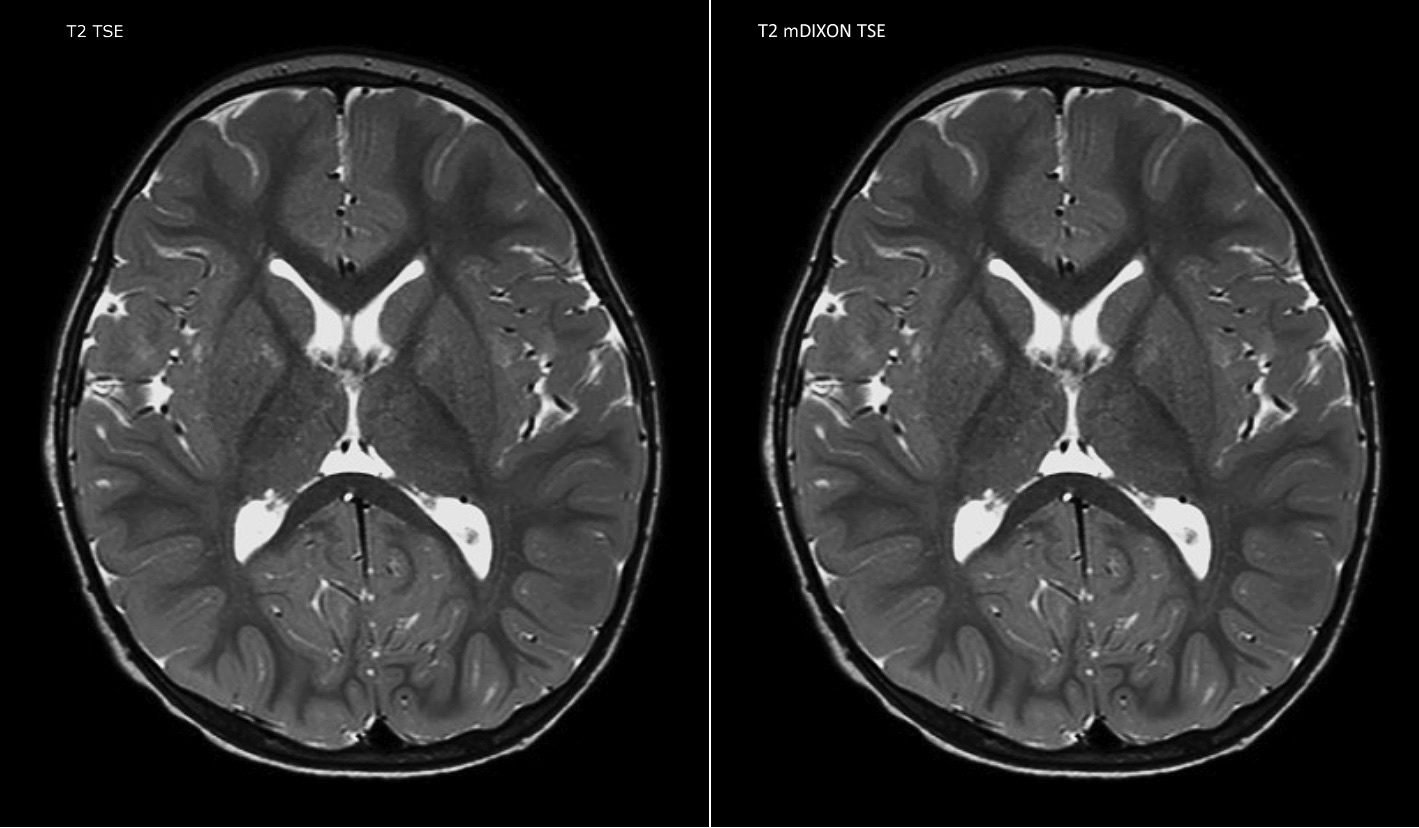

Routinely obtaining homogeneous fat suppression under virtually all conditions with mDIXON TSE

Philips mDIXON TSE is a two-point DIXON technique that separates water and fat signals, for time-efficient fat-free imaging, even in challenging neuro anatomy.

“mDIXON TSE has been one of the most significant improvements in imaging sequences that we have utilized to date at PCH,” says Dr. Miller. “Its multi-parametric acquisition allows us to obtain fat suppressed images and equivalent non-fat suppressed T2 images all in the same sequence. In addition, prior methods of fat suppression could be artifactually corrupted by poor patient anatomy or poor operator application, but with mDIXON we now have a robust and reliable method of fat suppression.”

Fat saturation is historically challenging at the ends of fields of view, especially in total spine imaging and in difficult patient anatomy such as the lower regions of the neck. “Due to the unique fat suppression capabilities of mDIXON, however, these challenges no long apply,” says Dr. Miller. “We routinely obtain homogeneous fat suppression under virtually all conditions. It has also led to some efficiencies by not having to repeat sequences because of that technical failure.”

mDIXON TSE makes a difference

“mDIXON TSE is most useful in patients with lesions or abnormalities in the soft tissues such as the face and neck, and for patients with contrast enhancing abnormalities that are mostly visible with fat suppression,” says Dr. Miller. “All our spine imaging now routinely contains mDIXON water-only T2 images, and this allows us to identify pathology that may be obscured by non-fat suppressed imaging such as injuries of the bone. And it’s not necessary to obtain additional standard TSE T2 images because the in-phase mDIXON images are equivalent to standard TSE T2 images.”

“mDIXON TSE has increased our diagnostic confidence in ruling in or ruling out abnormalities in which fat suppression is critical to diagnosis, such as metastatic disease or osseous abnormalities.”